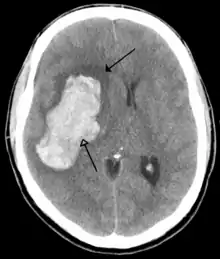

| CT scan of the brain showing a prior right-sided ischemic stroke from blockage of an artery. Changes on a CT may not be visible early on.[1] | |